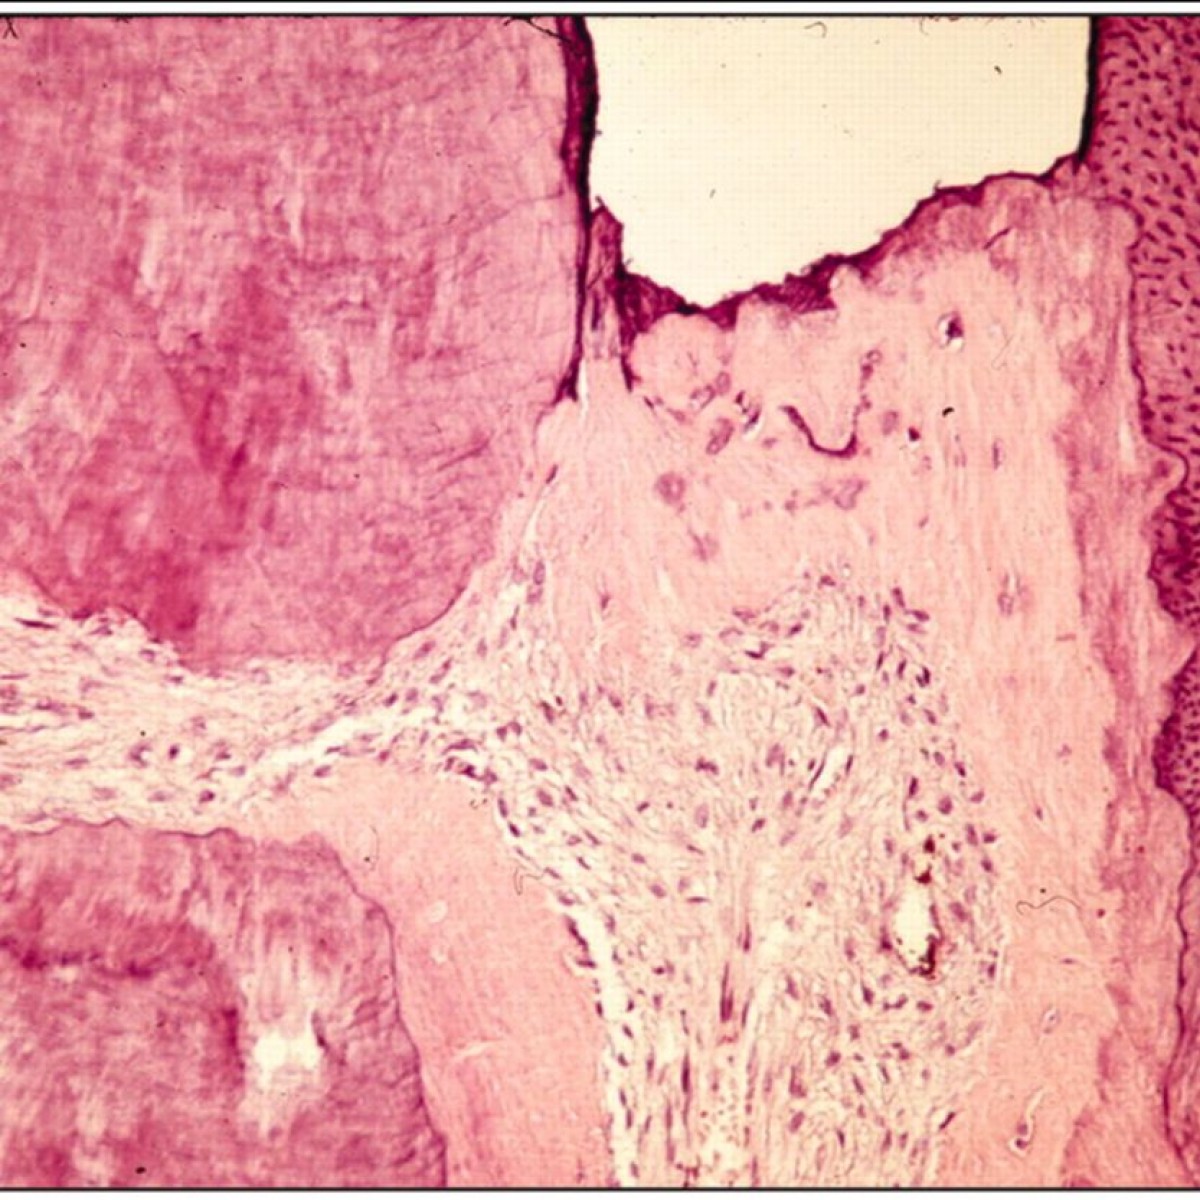

Diseases of the dental pulp often have an infectious origin, and treatments are aimed to control infections of the root canal system. Endodontic treatment principles originally evolved on the basis of trial and error, and only in recent decades have scientific methods been adopted to support clinical strategies. Yet, relevant research on the disease processes, their diagnoses, and efficient treatment are rare in the endodontic literature. Hence, the advancement of biologically based knowledge significant to clinical endodontics has been slow. Therefore, many differences of opinion still prevail in this field of dentistry. This review highlights and analyzes the background of some of the more heavily debated issues in recent years. Specifically, it deals with disagreements regarding the clinical management of pulpal exposures by caries in the adult dentition, definitions of success and failure of endodontic therapy, and causes of and measures to control infections of the root canal system. Clearly, a most apparent gap in the published endodontic literature is the lack of randomized clinical trials that address the more significant controversial matters relating to the management of pulpal wounds, medication, and the number of appointments required for the treatment of infected root canals. However, trials in endodontics require extremely long follow-up periods if valid conclusions are to be generated. Therefore, it is not to be expected that there will be rapid solutions to these issues in the foreseeable future.

Lesions of the pulp are often infectious, and treatments involve several critical steps that are aimed to restrain infections of the root canal system in teeth. Originally, treatment methodologies in endodontics, like those in many other dental disciplines, evolved based on trial-and-error observations, and only in recent decades have scientific methods been adopted to support clinical strategies. Yet, research reports focusing on issues relevant to the disease processes of the pulp and how they can be diagnosed and managed effectively are rare in the endodontic literature. An assessment of articles appearing in leading endodontic journals reveals that technical aspects of the testing of instruments and filling materials, often by in vitro evaluations in extracted teeth, tend to be the dominating topics (Wu and Wesselink, 1993; Eriksen et al., 2002). As a consequence, the advancement of biologically based knowledge significant to clinical endodontics has been slow. Irving Naidorf (1972), in a critical review on contemporary issues in endodontics, observed: “The preoccupation of dentists with techniques has channeled dentistry (including endodontics) into a state of technical excellence that often is not accompanied by a biological awareness of the basic pathologic problems with which we are dealing or the biologic consequences of our therapy. The schism between clinicians and basic scientists is propagated by a tendency of each group to confer with themselves rather than with each other.” The past 30 years have brought little change, and only modest amounts of the accumulated biological knowledge have found clinical application in the endodontic arena. It is, therefore, not surprising that, in this field of dentistry, there are many contradictory views and opinions as to the proper management of endodontic disorders.

This review highlights and analyzes the background of some of the more significant issues that have been debated in the endodontic field in recent years. Specifically, this review discusses controversies regarding the clinical management of the disease processes associated with the vital and the non-vital dental pulp.